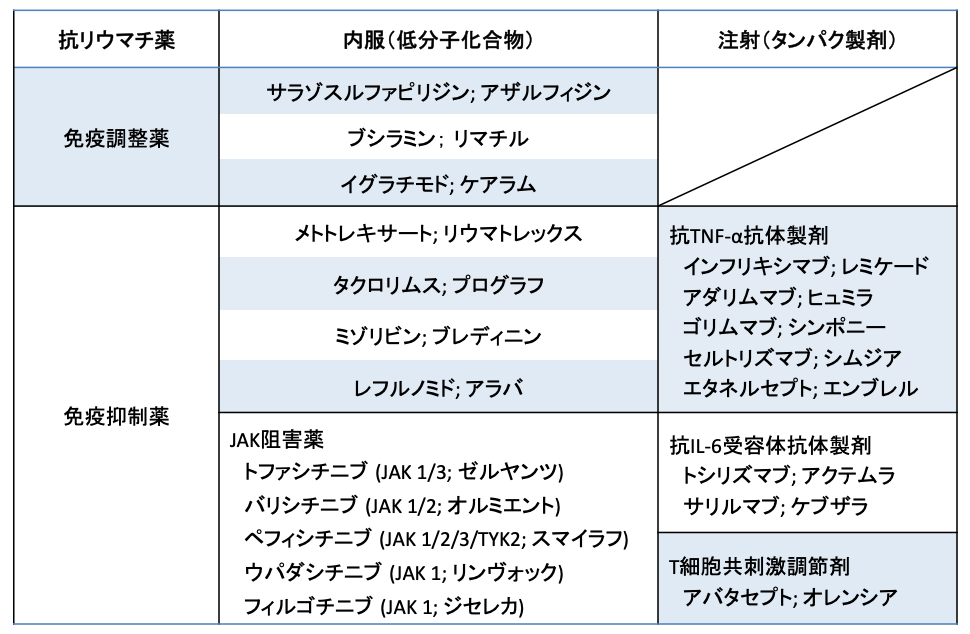

当外来で使用可能な抗リウマチ薬一覧

メトトレキサートを中心とした内服治療を主体に行いますが、充分な疾患活動性コントロールが得られない場合は、炎症を引き起こす物質であるサイトカイン(TNF-α、IL-6)や炎症を引き起こす細胞(T細胞)を抑制する作用をもつ生物学的製剤(注射薬)の使用も検討します。

また、内服薬でも生物学的製剤と同等の効果を有するJAK阻害薬の使用を検討することもあります。